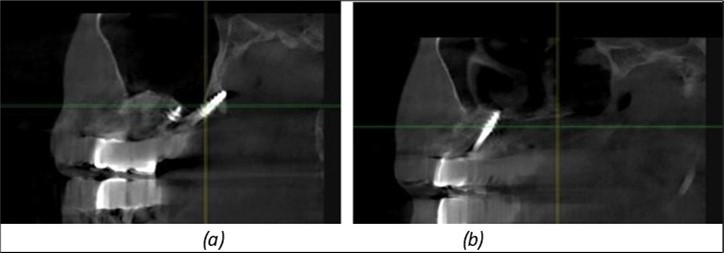

Figure 12.Implants fixed distally in quadrant 4 with fixation at the level of the mylohyoid line: (a) The most distal implant fixed in unaffected bone from the previous restoration; (b) The implant fixed in the area where the two stage implant was removed.

Implants fixed distally in quadrant 4 with fixation at the level of the mylohyoid line: (a) The most distal implant fixed in unaffected bone from the previous restoration; (b) The implant fixed in the area where the two stage implant was removed.